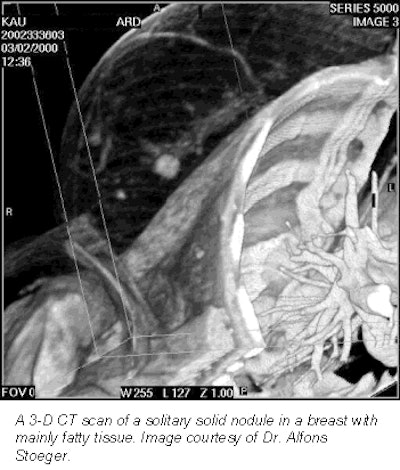

According to the results, breast CT found solitary solid nodules (>1.5 cm) in four patients. Single or multiple cysts (>5 mm) were found in eight patients, and macrocalcifications (>3 mm) were found in six women. Breast CT could not discern microcalcifications, which had been previously identified with mammograms, because of limited spatial resolution, Stoeger said.

The group concluded that CT was not useful for detecting microcalcifications, but that the modality may have potential for preoperative planning.

"We think that there may be a potential for this method in preoperative planning of breast disease (including the axilla) in the follow-up of certain benign masses, or even in planning radiotherapy after breast surgery," Stoeger said. "This does not mean that a CT scan should be performed for these reasons. But if these patients get a scan for other reasons, and the data exists, it could be post-processed and used for these issues instead of other time-consuming and expensive exams."